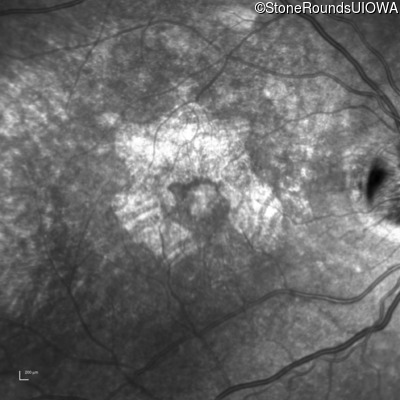

Infrared Fundus Photograph - Right - 20/32 +2

Exemplar